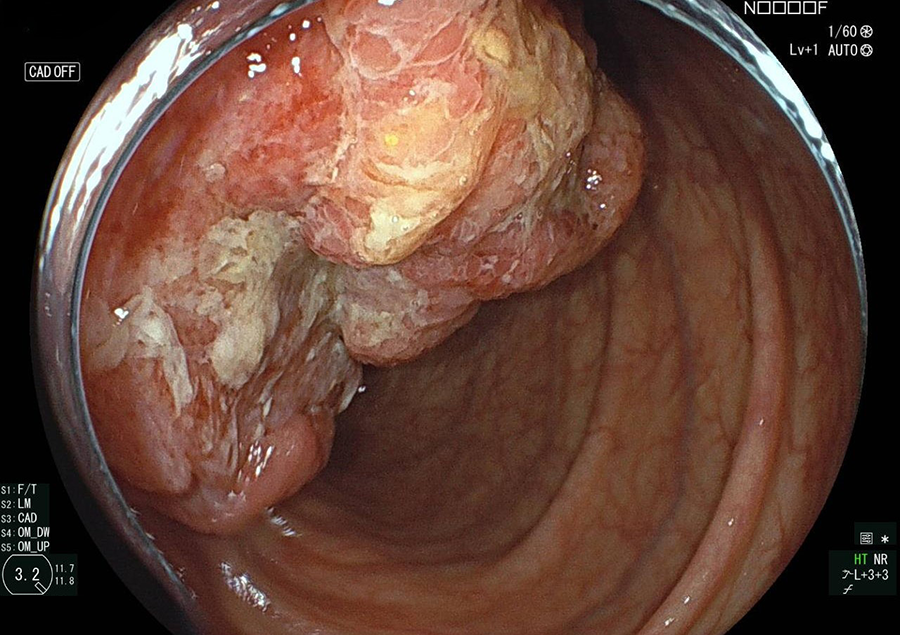

大腸カメラはポリープやがんの発見と診断に、最も精度の高い検査法です。

近年、大腸がんが急速に増加していますが、がんの芽となるポリープ(腺腫)、一部の早期がんは、大腸カメラによる内視鏡治療で完治させることが可能です。

大腸カメラ検査でわかる病気/病変

一般的に大腸ポリープのうち、約5%が早期がんといわれ、また良性のポリープもがんの発生母地になるといわれています。

そこで当院では大腸カメラ検査時にポリープや早期がんが発見された場合は、可能な限り積極的にその場で切除しております。